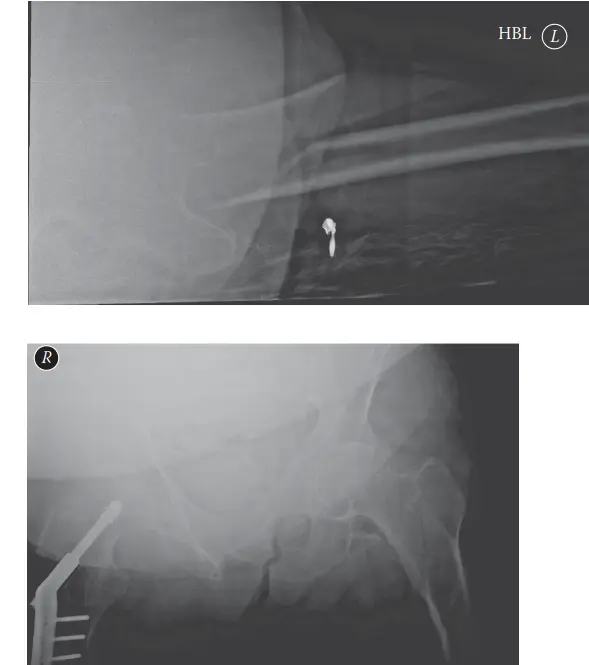

الأشعة السينية (X-rays):

- تُعد الخطوة الأولى والأساسية لتشخيص كسر تحت المدور.

- يتم التقاط صور بالأشعة السينية للورك المصاب والحوض، بالإضافة إلى صور أمامية وجانبية لعظم الفخذ بالكامل (بما في ذلك مفصل الورك والركبة).

- تساعد هذه الصور في تحديد نمط الكسر، درجة التفتت، وجود أي تشوهات سابقة، أو وجود أجهزة تثبيت قديمة.

- في بعض الأحيان، قد يُطلب تصوير عظم الفخذ المقابل غير المصاب لتقييم الانحناء الطبيعي للعظم والمساعدة في التخطيط الجراحي.

التصوير المقطعي المحوسب (CT Scan):

- يُستخدم في حالات الكسور المعقدة أو المفتتة بشكل كبير، خاصة إذا كان الكسر يمتد إلى الحفرة الكمثرية (Piriformis Fossa) أو المدور الكبير.

- يوفر صورًا تفصيلية ثلاثية الأبعاد لنمط الكسر، مما يساعد الجراح على فهم التشوه بشكل أفضل وتخطيط استراتيجية الرد وتثبيت المسمار النخاعي.

- يمكن أن يساعد في استبعاد كسور AFFs المخفية في الفخذ المقابل.